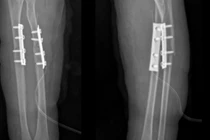

Ngã xe đạp trẻ 7 tuổi suýt mất vận động vì gãy kín

Gãy xương ở trẻ nhỏ nếu không được chẩn đoán và điều trị đúng cách có thể khiến xương lệch trục, biến chứng cứng khớp, hạn chế vận động cổ tay, khuỷu tay.